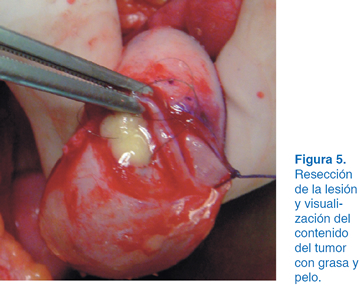

A los dos años del evento quirúrgico en el USG se apreció una tumoración en el ovario izquierdo con dimensiones de 10 x 12 cm (Figura 1). Se solicitó tomografía axial computarizada (TAC), observándose tumoración con densidades mixtas con diagnóstico probable de teratoma (Figura 2). Se optó por laparotomía exploradora donde se identificó el útero y se apreció tumoración dependiente de ovario izquierdo (Figura 3). Se realizó planeación de incisión (Figura 4), posteriormente tumorectomía (Figura 5) y salvamento de tejido ovárico (Figura 6). El reporte transoperatorio mostró teratoma monofásico con bordes libres de tumor.